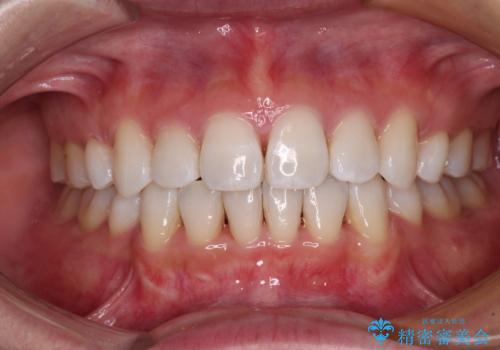

前歯のデコボコをインビザラインで改善

- 前歯のデコボコや八重歯の様になっていることを気にして来院された患者様です。

犬歯捻れて前方に飛び出しており、下顎前歯もそれに沿うようにデコボコとなっていました。

IPR(歯と歯の間を削る処置)によりスペースを獲得して上下顎前歯のデコボコを改善し、前歯が前方に突出しないように設定した上で、インビザラインにて矯正治療を行うこととしました。

途中体調を崩され、長い期間矯正治療を休むことになったため4年半ほどの治療期間がかかりました。